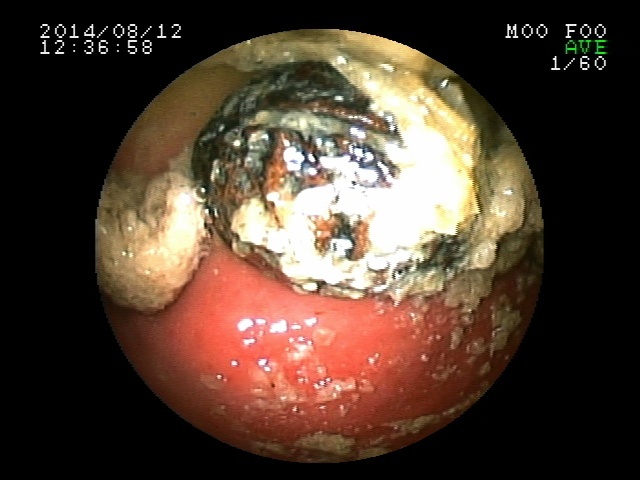

もし腸に流れてしまったら腸閉塞を起こす可能性の高いサイズだったので、すぐに内視鏡を入れて摘出しました。内視鏡では種以外に爪楊枝やビニールもみつかり、すべて内視鏡で摘出しました。

上の画像はCTの断層の画像ですが、下の画像は3D校正したCT画像です。見事に種が写ってますね。一番下は内視鏡で摘出しているタネです。胃内異物はとても多い病気ですが、胃内にある場合は、よほど大きくなければ手術ではなく内視鏡で摘出しています。